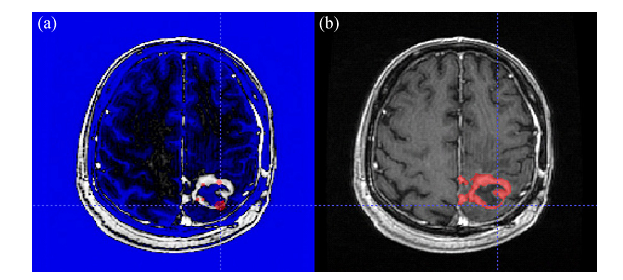

همچنین بخشی از نتایج شبیه سازی ها در ادامه نشان داده شده است.

تومور مغزی